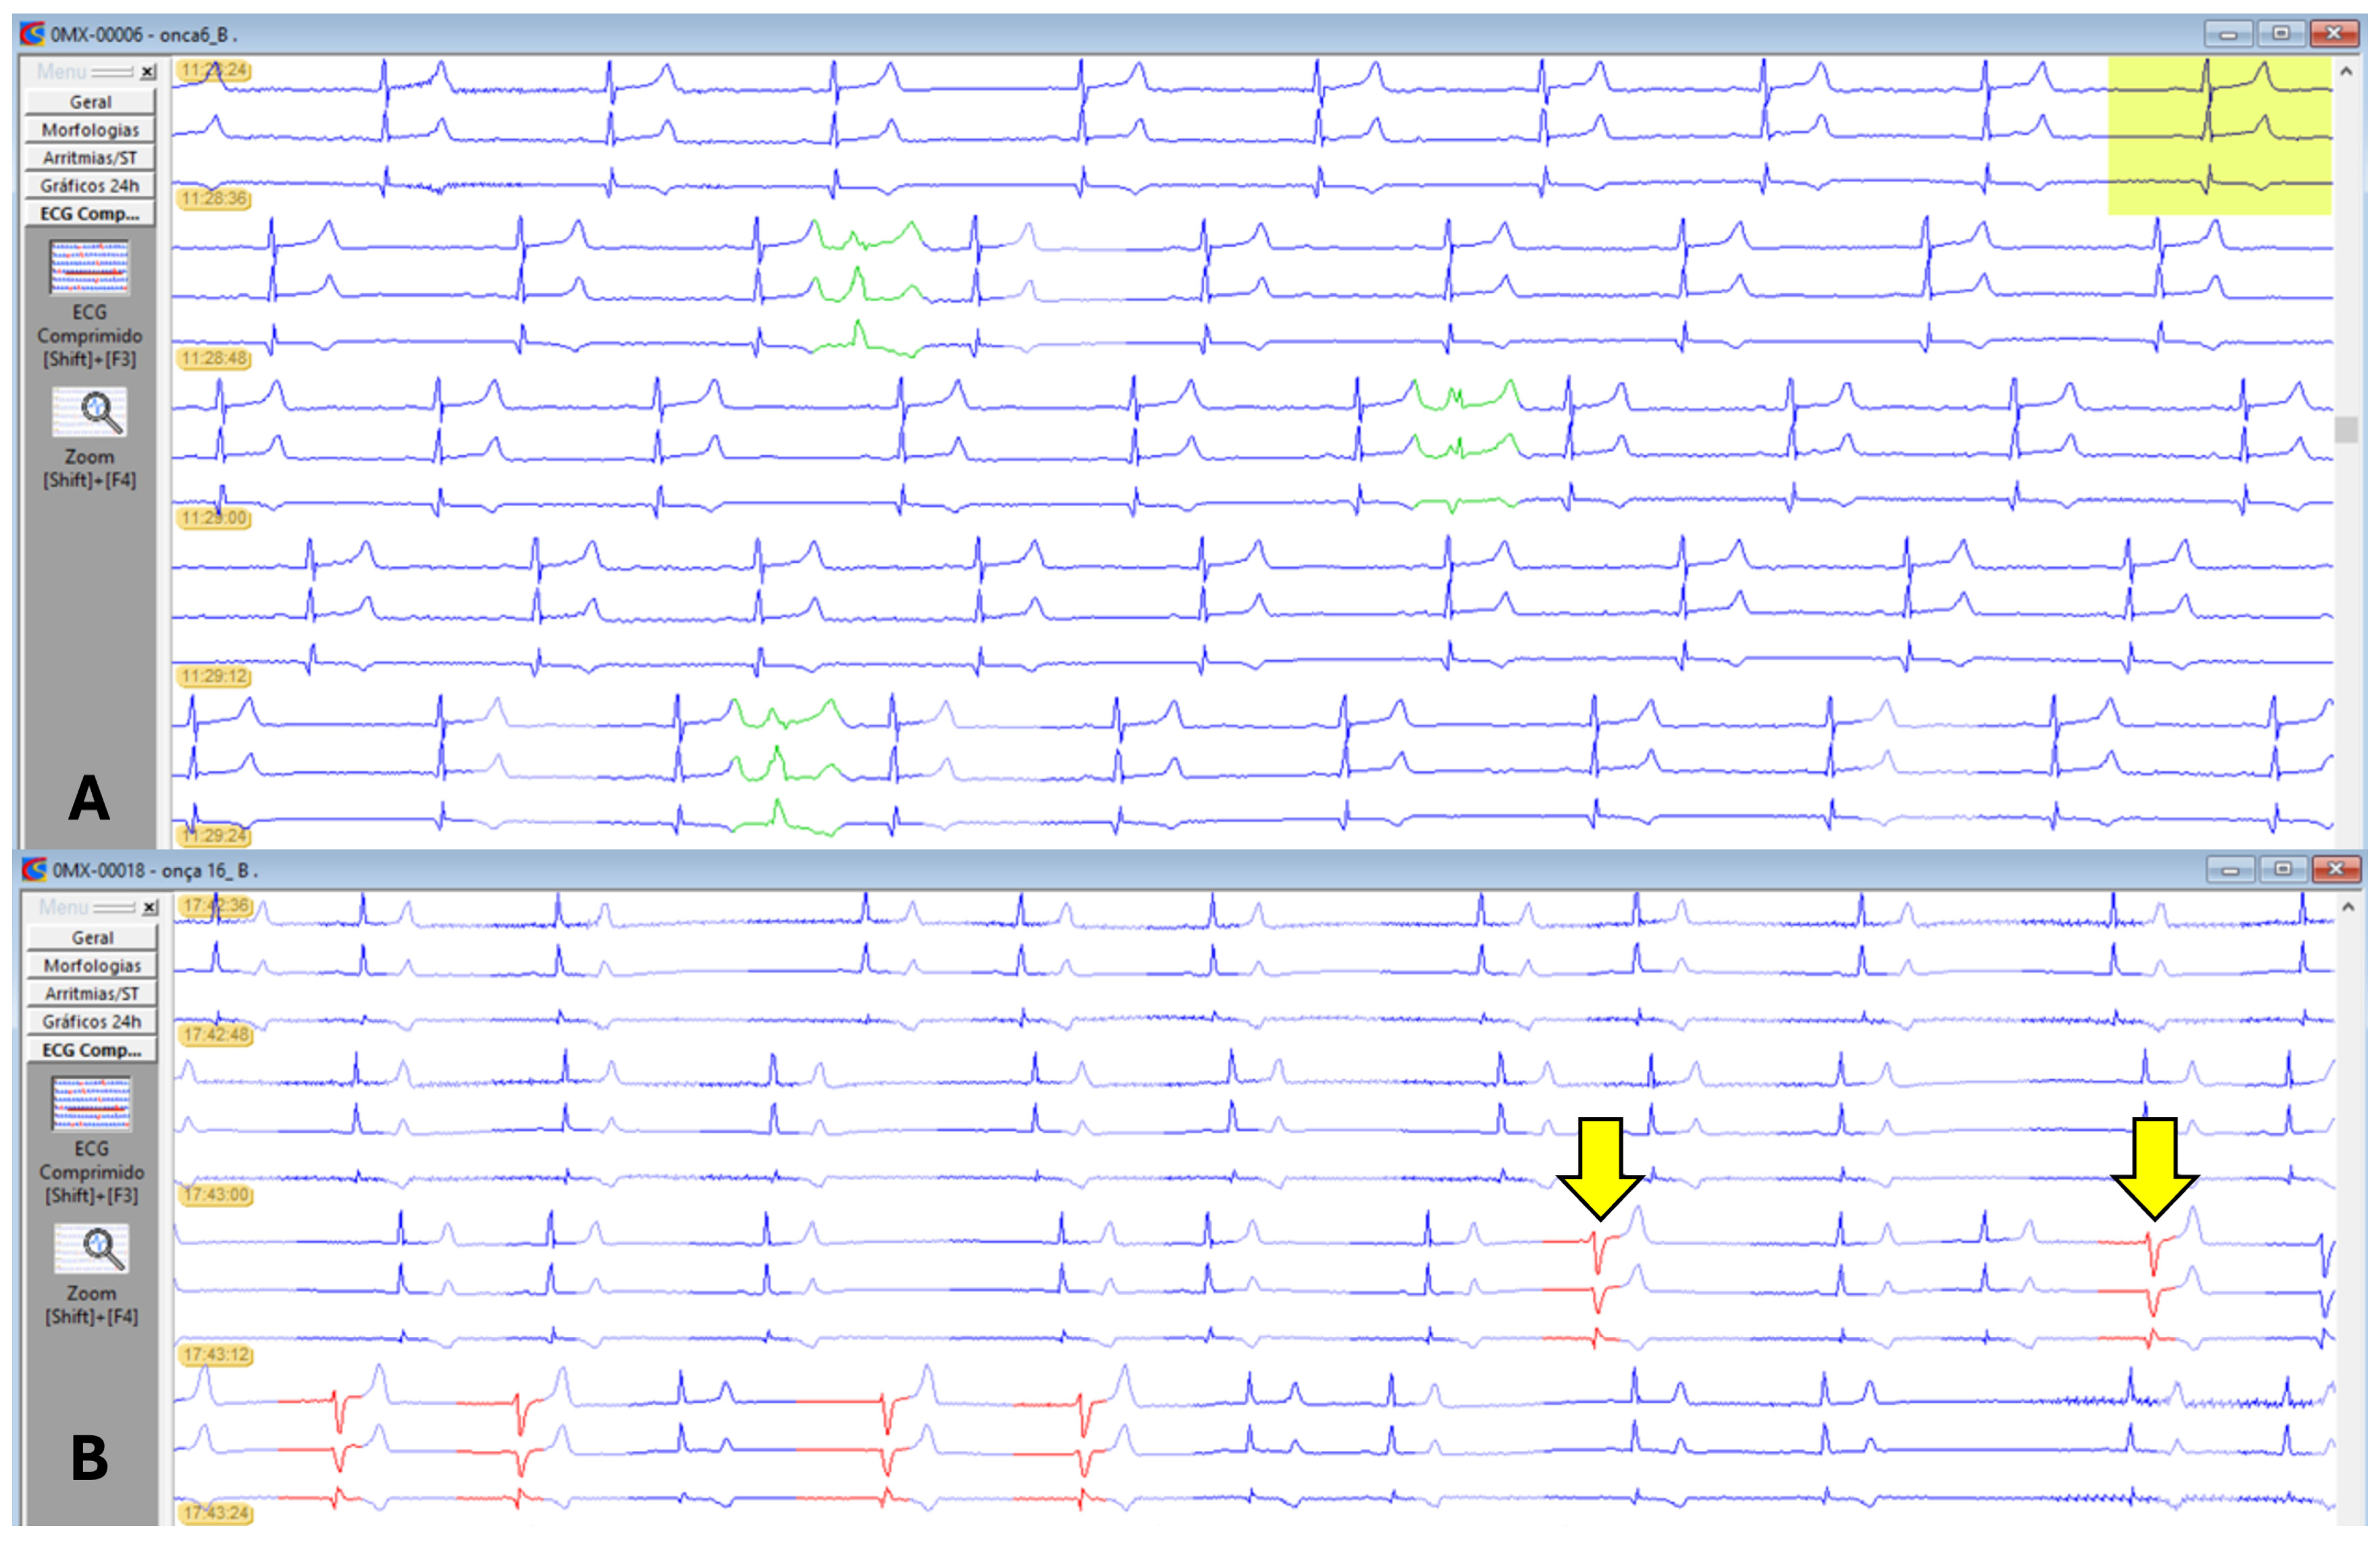

All parameters evaluated in Holter electrocardiography are presented in Table 4. There was no significant difference between the groups evaluated. The animals’ profiles indicated a predominance of the parasympathetic autonomic nervous system, with greater heart rate variability, evidenced by elevated rMSSD and pNN > 50% values, as well as SDNN, SDANN, and SDNNIDX, which indicate greater variability as they deviate from zero. However, five animals, two females and three males, exhibited a sympathetic profile, contributing to the reduction of rMSSD in G1 and G4. The dominance of patients with a tachogram profile is represented by image (B) in Figure 5.

One male, belonging to both G1 and G4, presented 35 events of premature supraventricular complexes. One female, included in G2 and G3, exhibited a short period of ventricular bigeminy (4 events) and 17 isolated episodes of monomorphic premature ventricular complexes (PVCs) of left ventricular origin (Figure 6).

Figure 6. Holter electrocardiographic recordings in jaguars anesthetized with medetomidine and ketamine. (A): Sinus rhythm represented in three channels (C1, C2, and C3) in blue. Presence of three supraventricular ectopic complexes in green. (B): Sinus arrhythmia represented in three channels (C1, C2, and C3) in blue. Presence of two isolated, monomorphic premature ventricular complexes of left ventricular origin (yellow arrows) and bigeminy events in other beats highlighted in red in the last line of the trace.